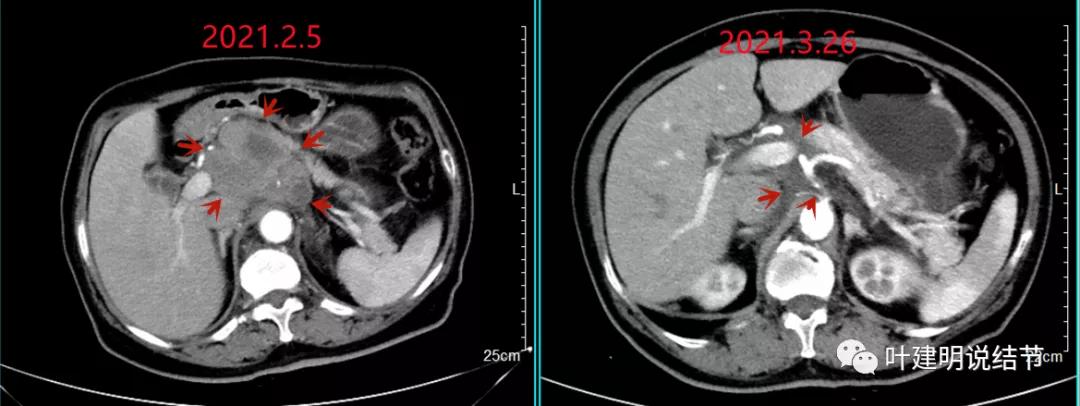

我们选择了“特瑞普利单抗加多西他赛加卡铂”的化疗加免疫治疗方案。我们来看经过一个周期治疗后肿瘤改善情况的对比:

上图左侧是治疗前的,右侧图像是差不多同一层面(因原肿瘤挤压,很难完全找出同一平面),可见病灶明显缩小改善了!下面是复查时的CT影像报告: